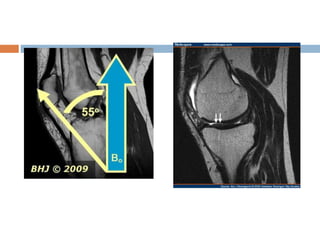

Magic angle artifact

 Seen most frequently in tendons and ligaments that

are oriented at a 55 degree to main magnetic field.

 Normally dipolar interaction between water

molecules in ligaments are strong.

 Which implies that T2 relaxation is very fast leading

to signal loss.

 Dipolar interaction go to zero.

 Solution

 Lengthen TE

 Use T1 weighted sequences since T1 relaxation is

unaffected by this.

Magic angle artifact Seen most frequently in tendons and ligaments that are oriented at a 55 degree to main magnetic field.  Normally dipolar interaction between water molecules in ligaments are strong.  Which implies that T2 relaxation is very fast leading to signal loss.  Dipolar interaction go to zero.  Solution  Lengthen TE  Use T1 weighted sequences since T1 relaxation is unaffected by this.